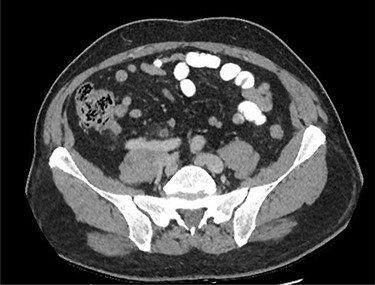

He had ongoing episodes of fever (38.1, 38.8 and 38.5°C) on days 3 and 4 post-operatively, so his antibiotics were escalated to piperacillin/tazobactam and metronidazole, according to microbiologist advice. However, on day 5 post-operation, he was still complaining of a severe tenderness on the right iliac fossa, associated with guarding, he was diaphoretic and febrile and clinical examination showed a tender lump in the right inguinal region. A CT of the abdomen and pelvis was performed to assess for a deep-seated collection, and it showed post-operative changes in the right lower quadrant at the site of recent appendicectomy, with small foci of poorly encapsulated fluid in the right lower quadrant with a further more well-defined 7 cm fluid collection/abscess extending from the right lower quadrant into a right inguinal hernial orifice and extending into the hernia sac (Fig. 2).

CT of the abdomen and pelvis demonstrating a fluid collection/abscess extending into a right inguinal hernia sac in (A) coronal (B) sagittal and (C) apical planes.